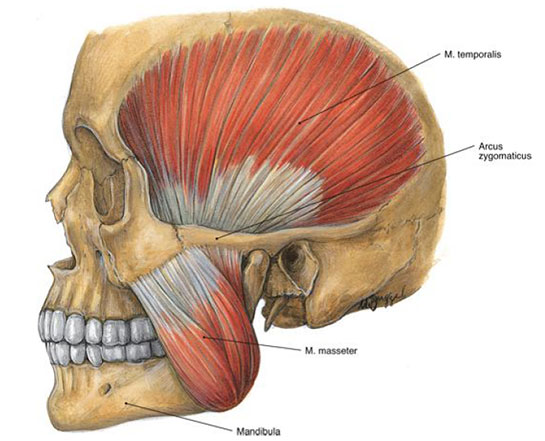

Çiğneme kasları, ağız içinde bulunan ve yiyeceklerin mekanik olarak parçalanarak sindirim sürecine hazırlanmasında önemli rol oynayan kas gruplarıdır. Bu kaslar, yalnızca yiyeceklerin parçalanmasında değil, aynı zamanda konuşma, yutma ve yüz ifadelerinin oluşumunda da kritik bir işlev üstlenmektedir. Çiğneme Kaslarının Anatomik Yapısı Çiğneme kasları, başın yan tarafında yer alan birkaç ana kas grubundan oluşur. Bu kaslar arasında en önemli olanları şunlardır:

Bu kaslar, çiğneme hareketlerini gerçekleştirirken, alt çenenin yukarı, aşağı ve yan hareketlerini sağlamaktadır. Çiğneme Kaslarının Fonksiyonları Çiğneme kasları, aşağıdaki temel fonksiyonları yerine getirir: